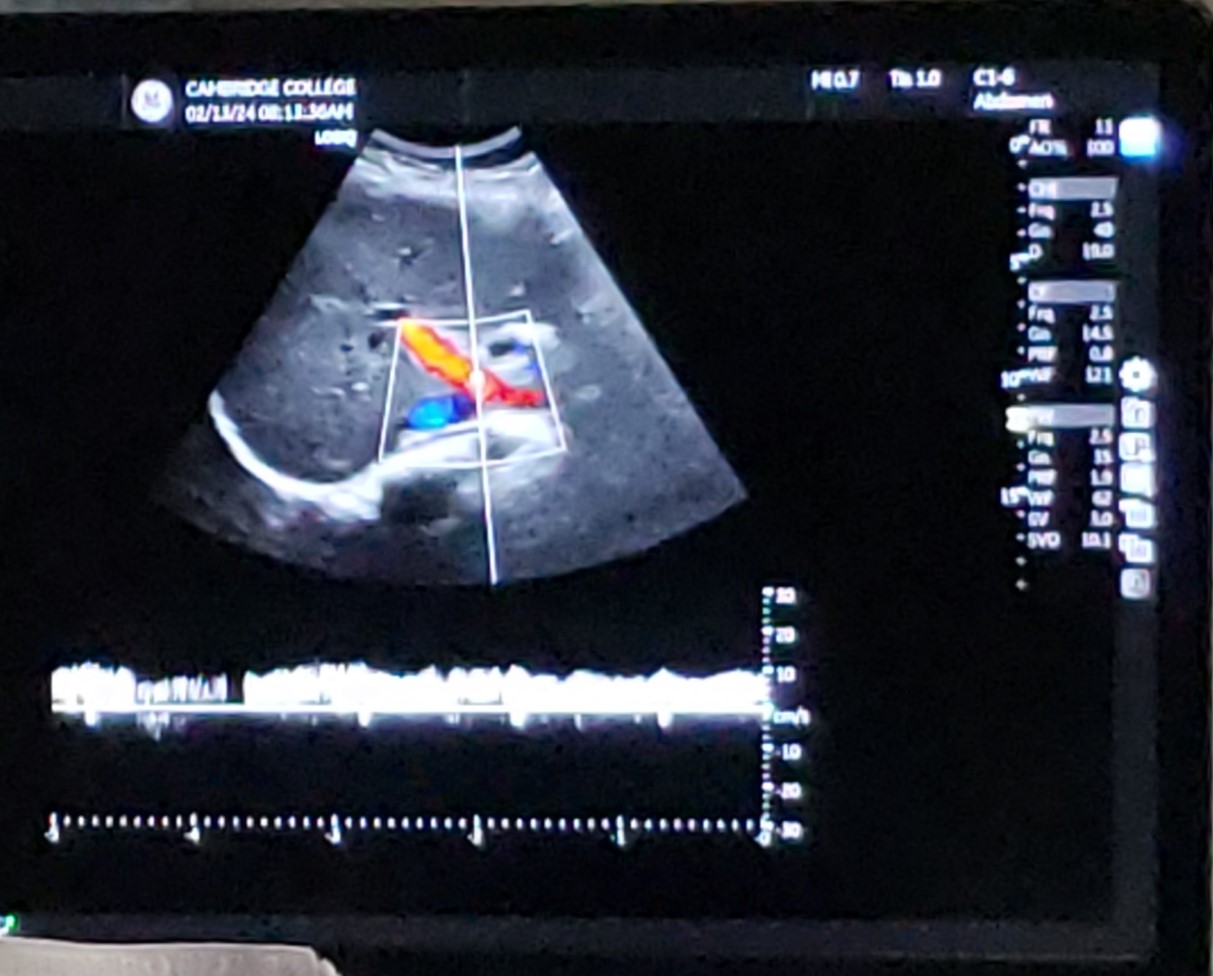

15

New cards

Trans RLL w/ MPV - PW doppler